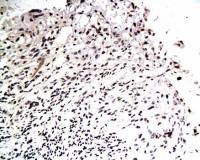

Pumilio 2 antibody [N1N2], N-term detects Pumilio 2 protein at cytoplasm on mouse kidney by immunohistochemical analysis.

Sample: Paraffin-embedded mouse kidney.

Pumilio 2 antibody [N1N2], N-term (GTX107995) diluted at 1:500.

Antigen Retrieval: Trilogy™ (EDTA based, pH 8.0) buffer, 15min